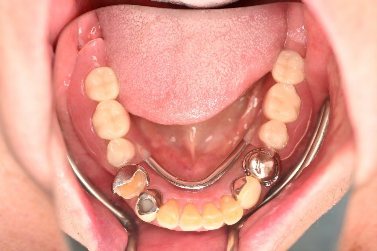

男性 Kさん 60代 (インプラント)

主訴

下の左右歯がないところに歯を入れたい。

治療内容

左右それぞれ3本歯がないところに2本ずつインプラントを埋入しました。

所感

上と下の歯の咬合接触がないすれ違い咬合です。上下義歯で対応するには最も難しいタイプの欠損状況です。治療開始前は、上下部分入れ歯が入っていましたが、入れ歯の安定が悪く、あちこちの歯茎に入れ歯が当たって痛く、満足に噛める状態ではありませんでした。上顎は、残ってる歯を活用するマグネット式総義歯を、下顎はインプラントを提案しました。上顎は、現在残っている歯の根管治療中です。上顎にマグネット式総義歯がはいれば、何でも食べられるようになります。

インプラント4本:¥363,000×4本=¥1,452,000(税込)

ポンティック2本:¥115,500×2本=¥231,000(税込)

合計:¥1,683,000(税込)

Before

▼初診時に使用していた部分入れ歯を装着したところ

▼インプラント埋入前

After

▼インプラント埋入後